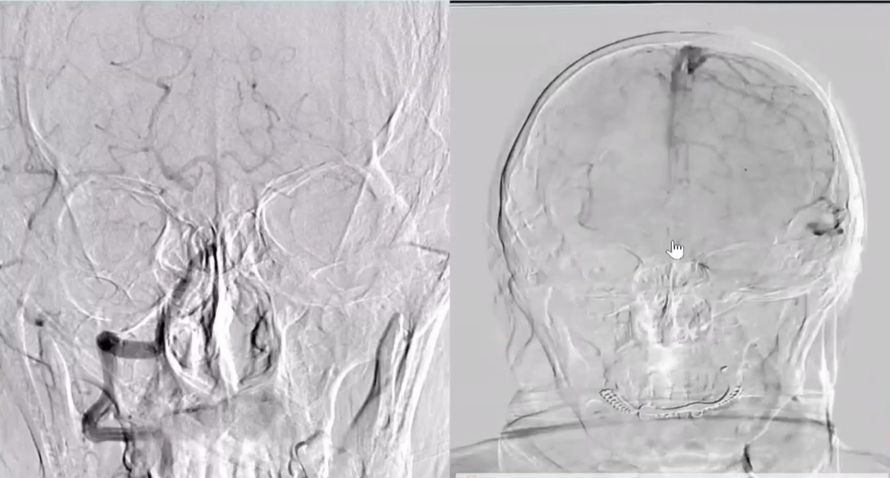

术前右侧椎动脉造影

病历夹什么径技·第152期|串联营病历夹:川陕大营_https://www.jmylbn.com_新闻资讯_第11张

病历夹什么径技·第152期|串联营病历夹:川陕大营_https://www.jmylbn.com_新闻资讯_第12张

病历夹什么径技·第152期|串联营病历夹:川陕大营_https://www.jmylbn.com_新闻资讯_第13张<<滑动查看下一张图片>>

术前左侧椎动脉造影

病历夹什么径技·第152期|串联营病历夹:川陕大营_https://www.jmylbn.com_新闻资讯_第14张

病历夹什么径技·第152期|串联营病历夹:川陕大营_https://www.jmylbn.com_新闻资讯_第15张

病历夹什么径技·第152期|串联营病历夹:川陕大营_https://www.jmylbn.com_新闻资讯_第16张

<<滑动查看下一张图片>>

左侧颈总动脉造影

病历夹什么径技·第152期|串联营病历夹:川陕大营_https://www.jmylbn.com_新闻资讯_第17张

右侧颈总动脉造影

病历夹什么径技·第152期|串联营病历夹:川陕大营_https://www.jmylbn.com_新闻资讯_第18张

病历夹什么径技·第152期|串联营病历夹:川陕大营_https://www.jmylbn.com_新闻资讯_第19张

病历夹什么径技·第152期|串联营病历夹:川陕大营_https://www.jmylbn.com_新闻资讯_第20张

左侧椎动脉起始部成形

病历夹什么径技·第152期|串联营病历夹:川陕大营_https://www.jmylbn.com_新闻资讯_第21张

病历夹什么径技·第152期|串联营病历夹:川陕大营_https://www.jmylbn.com_新闻资讯_第22张